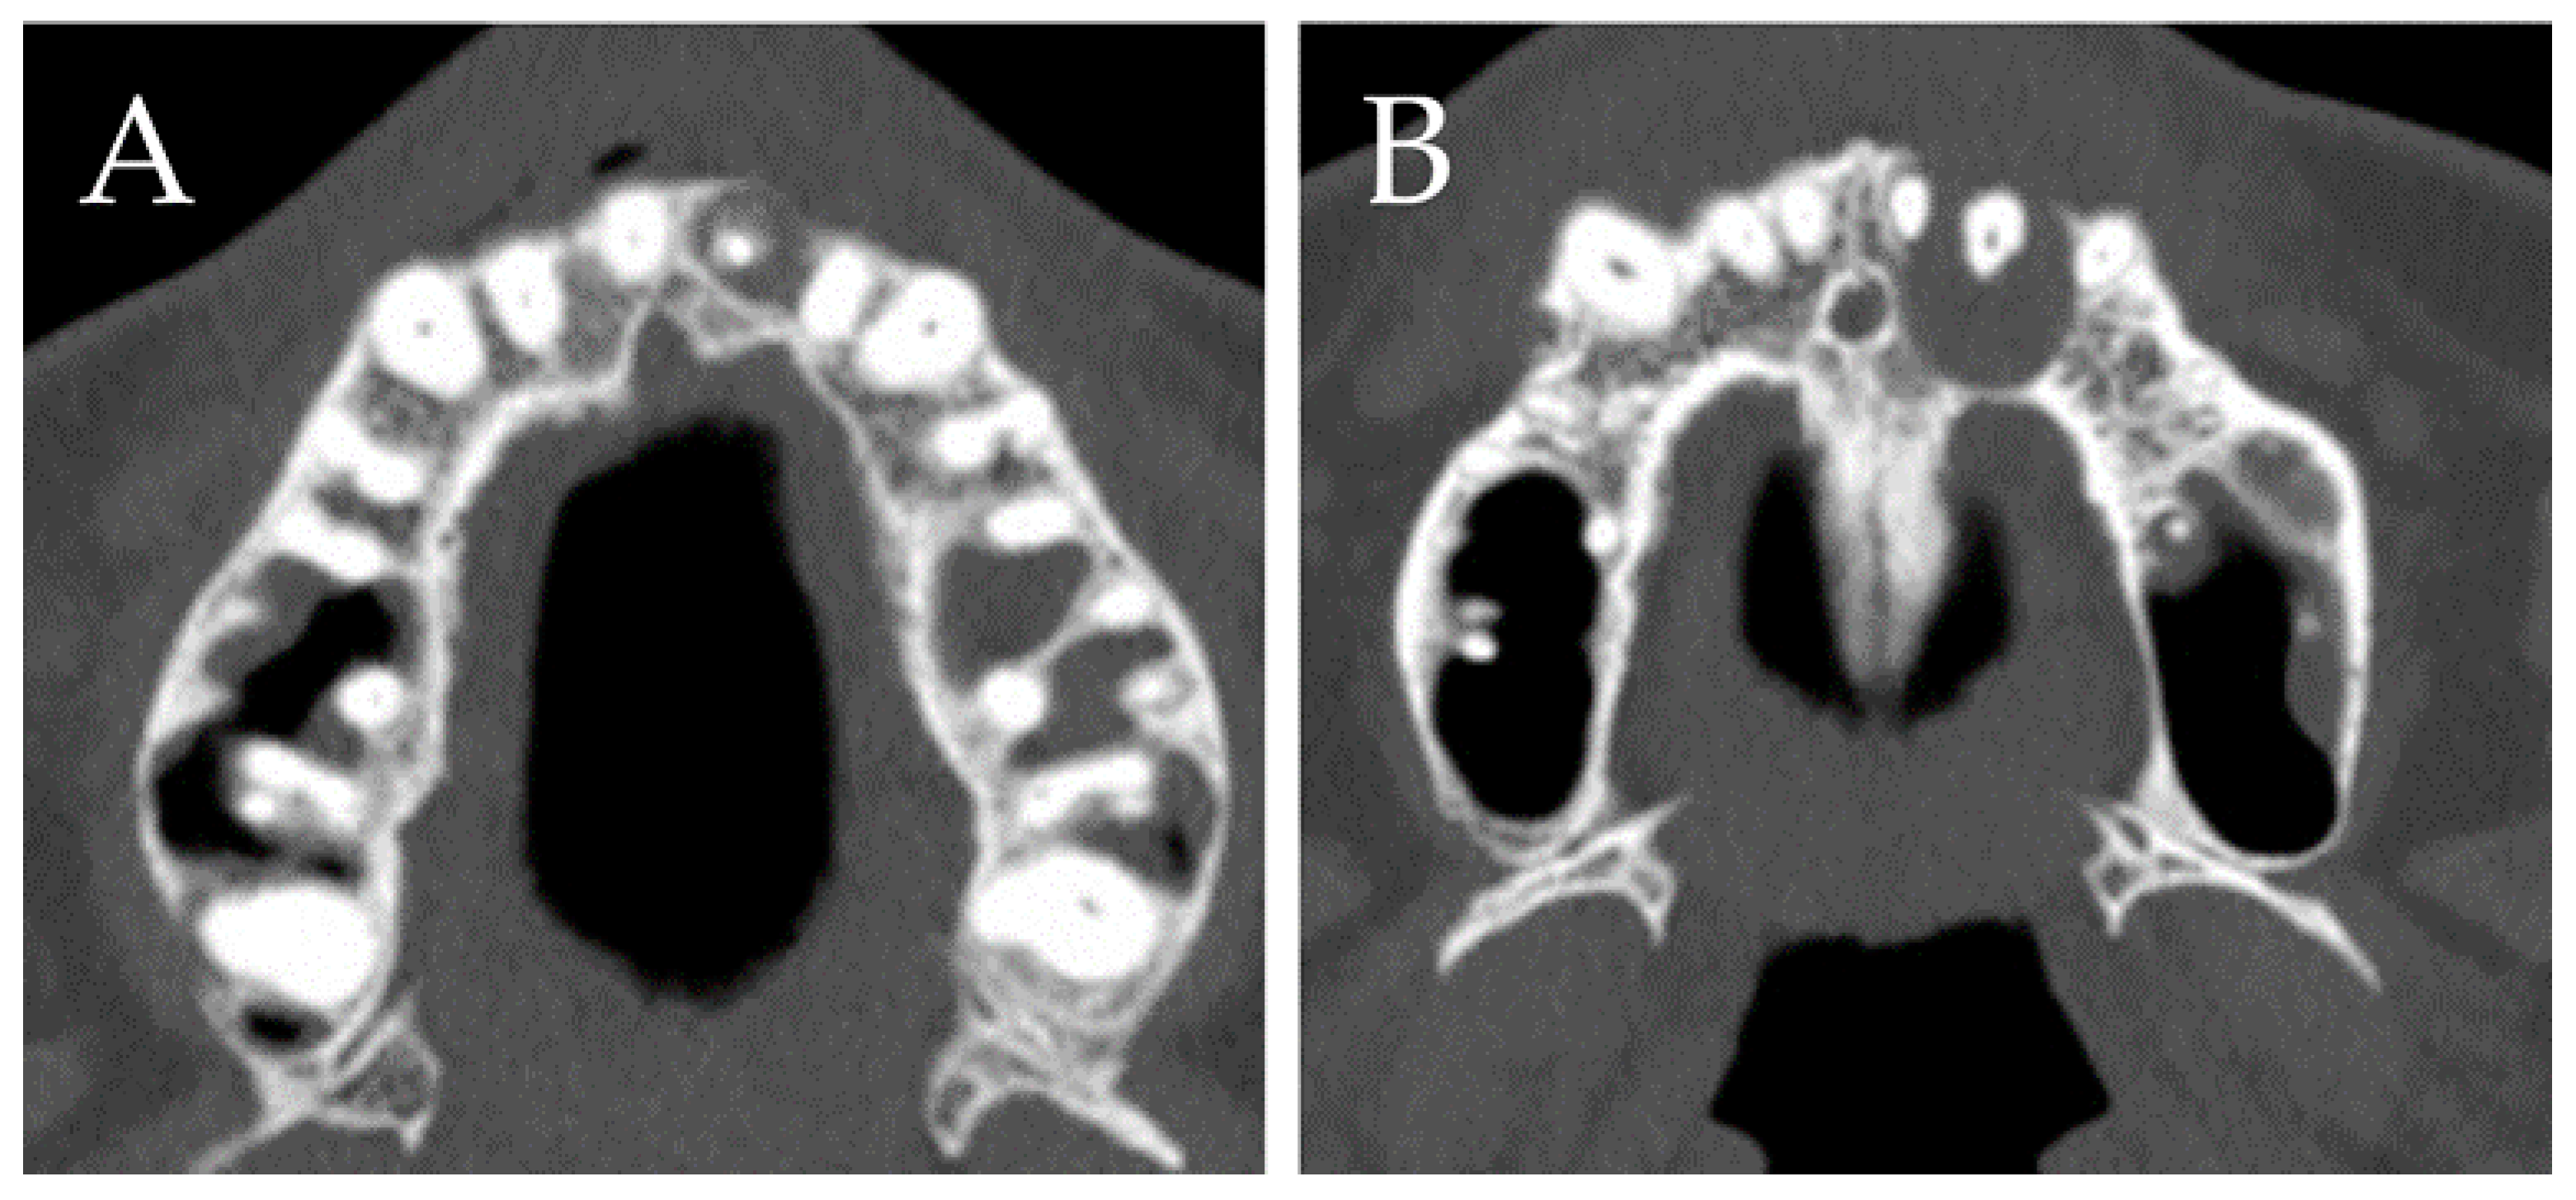

- Sukegawa, S.; Matsuzaki, H.; Katase, N.; Kawai, H.; Kanno, T.; Asaumi, J.I.; Furuki, Y. Morphological characteristics of radicular cysts using computed tomography. Odontology 2020, 108, 74–83. [Google Scholar] [CrossRef]